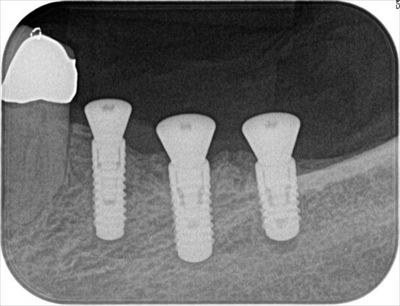

オペ終了時のレントゲン写真です。

スイス ストローマン社 ボーンレベルインプラントSLActive です。

手前はナロー、奥2本はレギュラーです。

インプラントの埋入を終えました。